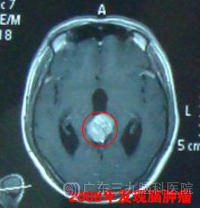

30岁的崔先生于2008年8月被检查出生殖细胞瘤。2008年5月,崔先生开始出现双眼视力下降、双耳听力下降,在当地医院诊断为生殖细胞瘤并梗阻性脑积水。www.999brain.com

2008年8月底,崔先生转入广东三九脑科医院治疗,在接受了脑室腹腔分流术后,于9月开始在广东三九脑科医院肿瘤综合治疗中心接受治疗,予以全脊髓放疗,颅内肿瘤60Gy,脊髓44Gy。2008年9月-09年2月行6疗程低毒性化疗,放化疗后复查MR示肿瘤明显缩小。2009年5月复查头颅MR示松果体区结节影较前稍增大,针对该病灶行X刀治疗。www.999brain.com